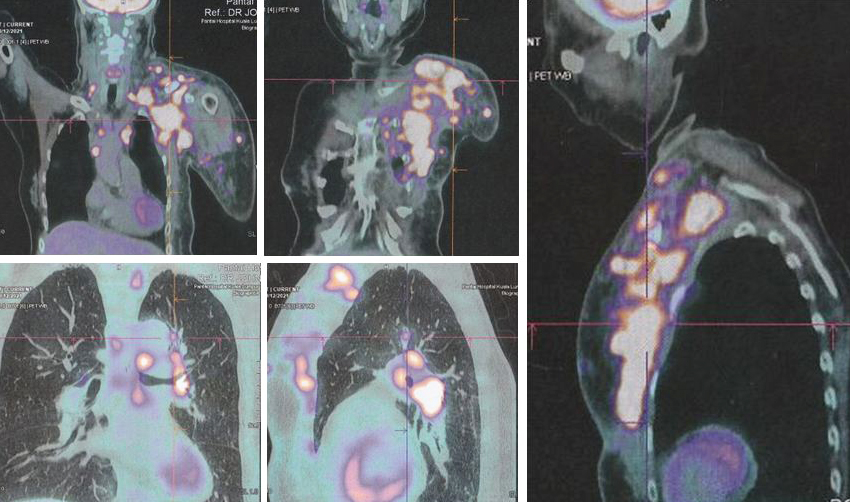

18.  Results blood test and PET scan at the private hospital in Kuala Lumpur were:

• Blood test – CEA = 8.3 (above normal).

• PET scan showed local recurrence at left chest well, with metastases to regional and distinct lymph nodes, subcutaneous nodules, lung, peritoneum and bones. There is minimal pericardial effusion, metastases cannot be excluded.

As demonstrated by the outcome of this case, Lucy had taken the wrong path. Twenty months after doing what she thought was the right things to do, Lucy’s cancer spread like wild fire. There were metastases to regional and distinct lymph nodes, subcutaneous nodules, lung, peritoneum and bones (see the pictures above).

I may say I could not believe what I saw in the PET scan – it was a terrible disaster indeed. Lucy had committed  a tragic mistake.